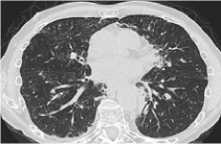

Примеры наиболее частых пульмонитов представлены на рисунке 1.

Пульмонит с диффузными изменениями по типу матового стекла, картина неспецифической интерстициальной пневмонии (НСИП)

Рисунок 1. Виды Л-ИЗЛ